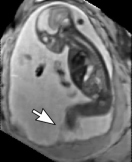

Reconstruction of Fetal Organs: Exemplary PVR and SVR reconstructions under motion introduced by kicking of the fetus are shown in Fig. 11. PVR reconstruction results show an improved visual appearance and less blurring in the region with severe motion artifacts (arrow). An example of a challenging clinical case with a kidney malformation in one of twin fetuses, is shown in Fig. 8. Our clinical partners confirmed that such complications are easier to examine and to quantify after PVR-based reconstruction.